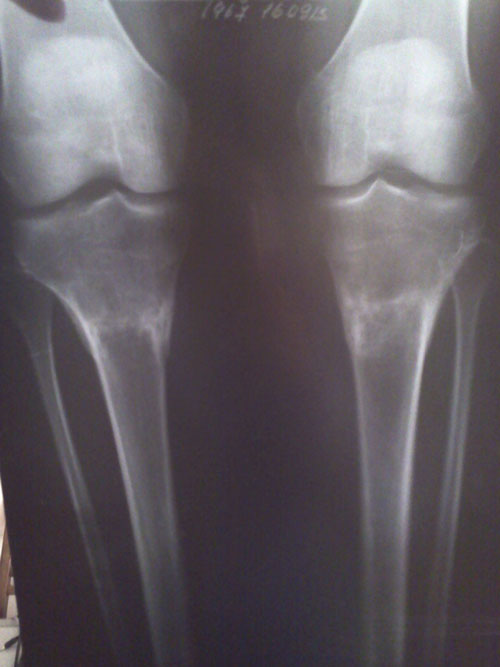

- Диагноз: О-образная деформация нижних конечностей

Здравствуйте, Настя! Мы рады, что у вас всё хорошо! Боль в местах перелома пройдёт со временем (мало времени прошло). По результатам рентгена, все ограничения снимаются! Можете позволить себе всё! И ждём фото ножек!!!Здравствуйте, Николай Николаевич!

Извините за позднюю отправку контрольных снимков (от 18 сентября) после снятия аппаратов. Дата операции 10 апреля 2013г., дата снятия - 25-26 июля 2013г.

Самочувствие хорошее, нагрузку контролирую, каблук 3см, походка нормальная. Но иногда болят места переломов. Будут ли какие-либо рекомендации ?